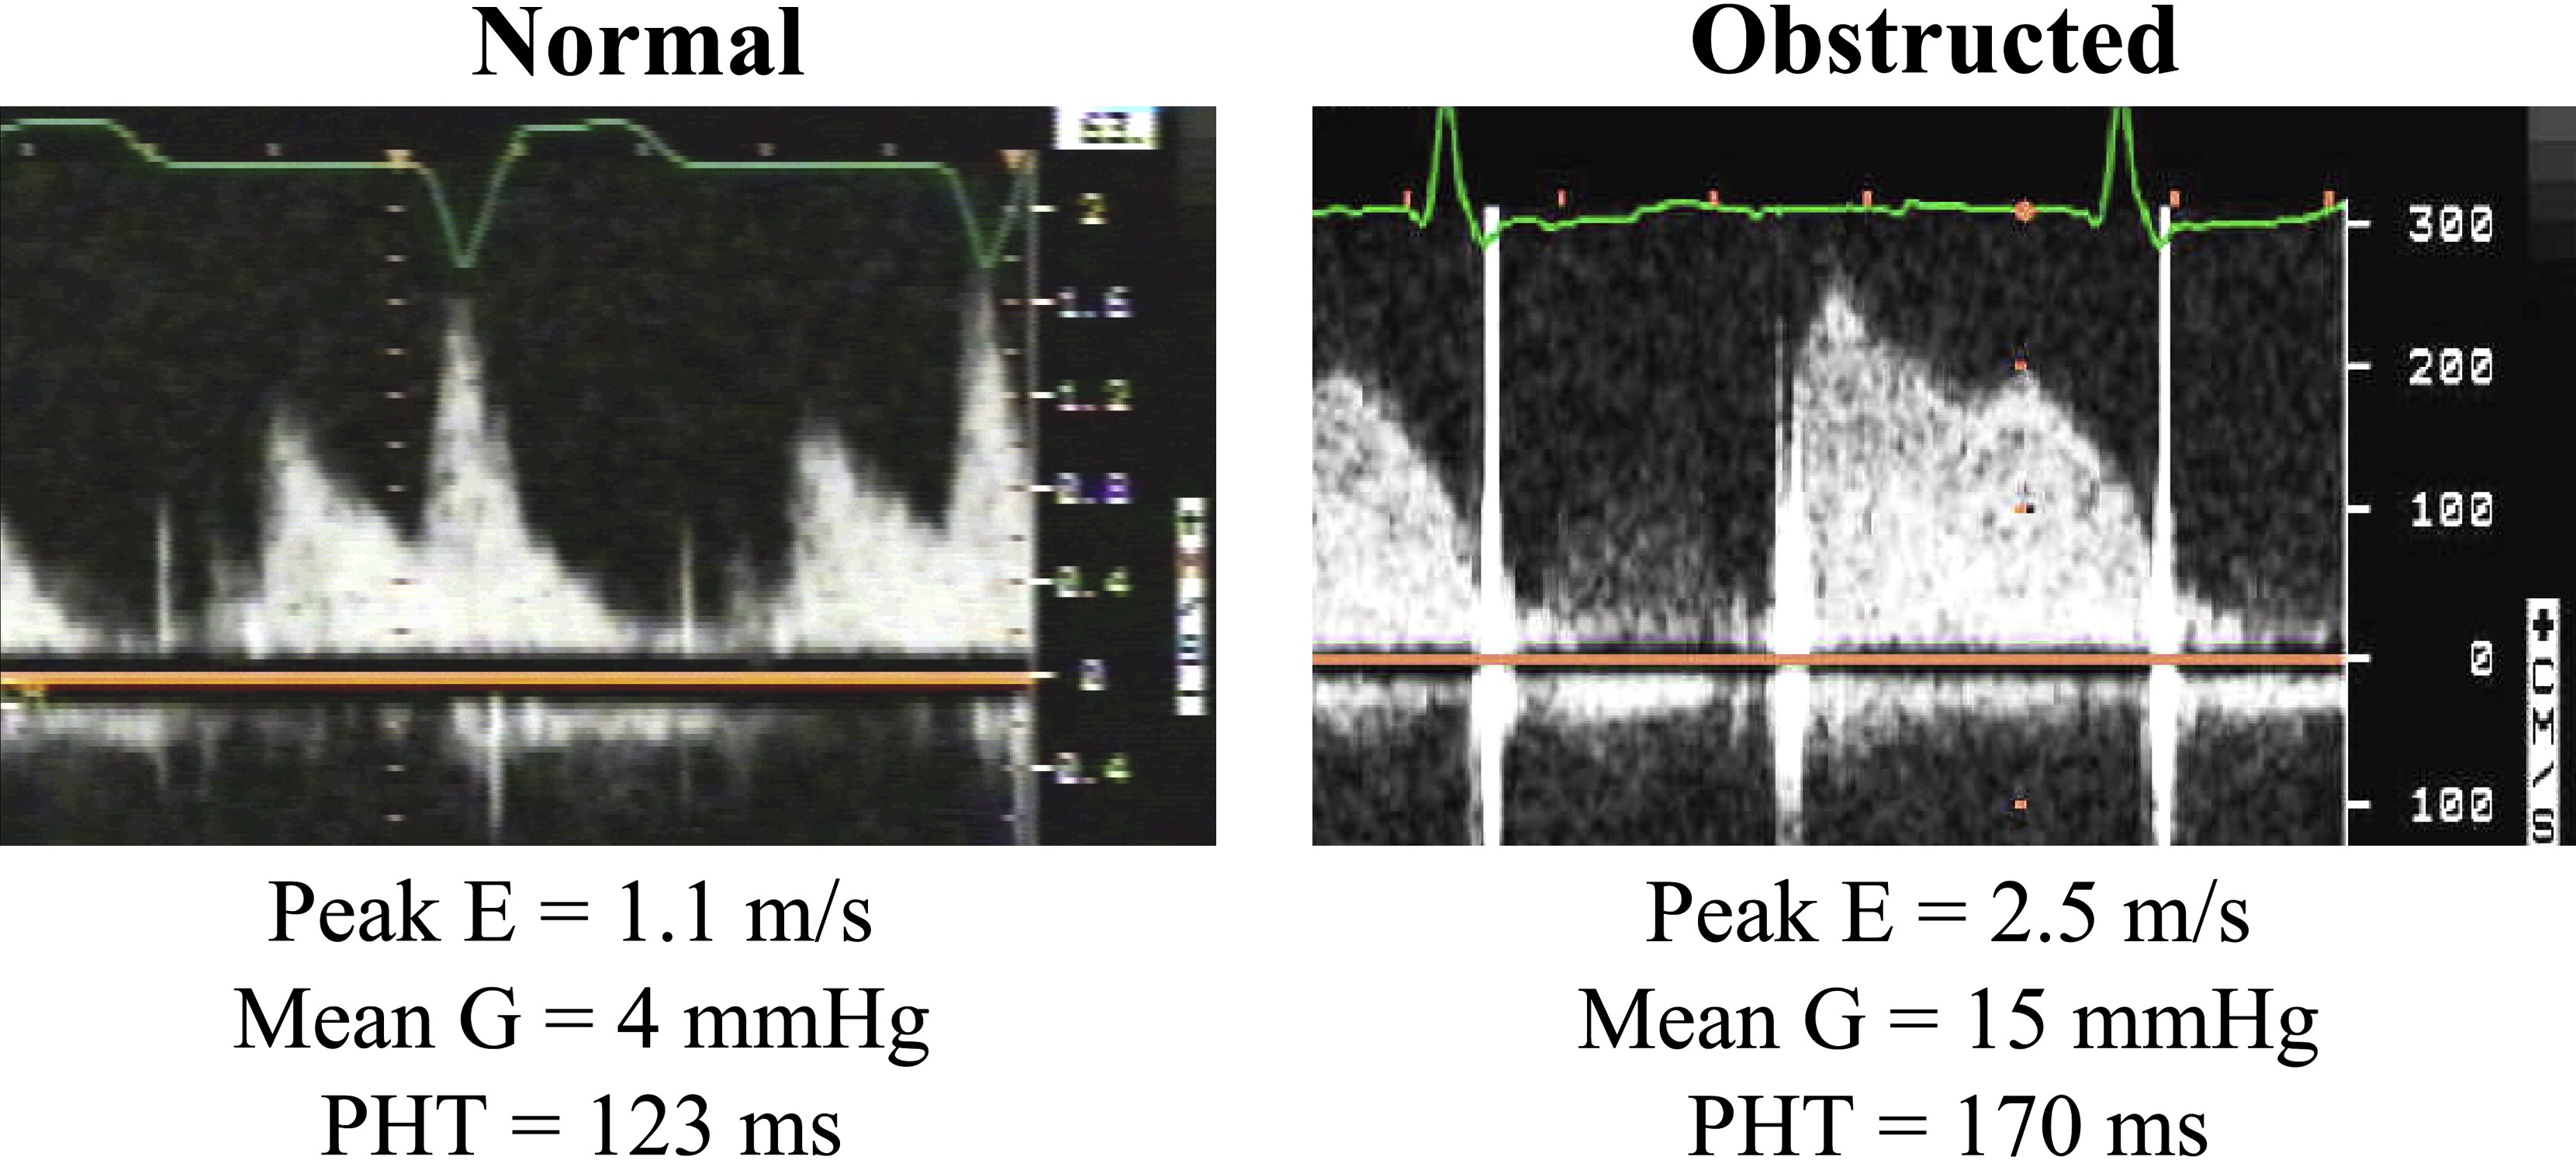

# Doppler Echo Evaluation of MVR 二尖瓣人工瓣膜

- Peak early velocity 峰值早期速度

- Mean pressure gradient 平均压差

- Heart rate at time of Doppler 多普勒检查时的心率

- Pressure Half-time 压力减半时间

# Doppler Parameters of Prosthetic Mitral Valve Stenosis 狭窄的指标

| Normal | Possible Stenosis | Suggests Sigificant Stenosis | |

|---|---|---|---|

| Peak velocity | < 1.9 m/s | 1.9-2.5 m/s | ≥ 2.5 m/s |

| Mean gradienty | ≤ 5 mmHg | 6-10 mmHg | > 10 mmHg |

| VTIPrMV / VTILVO | < 2.2 | 2.2-2.5 | > 2.5 |

| EOA | ≥ 2.0 cm2 | 1-2 cm2 | < 1cm2 |

| PHT | < 130 ms | 130 - 200 ms | > 200 ms |